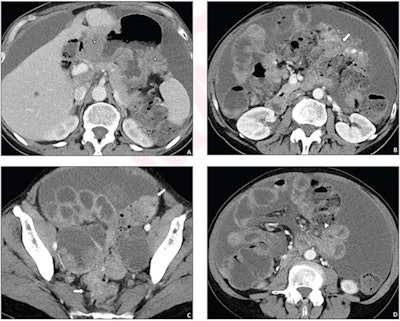

A 62-year-old woman who underwent pretreatment CT for suspected advanced ovarian cancer. A simple structured CT report described the presence of peritoneal implants in six anatomic locations. The disease was considered resectable based on the CT report, and primary debulking surgery was performed. However, the surgery yielded suboptimal resection. Axial contrast-enhanced images from pretreatment CT show disease involvement of sites of residual disease at surgery that were not mentioned in the report, including the gastric wall (stars, A), colonic wall (arrows, B and C), and small bowel mesentery (arrowhead, D). Images and caption courtesy of AJR.The investigators surveyed eight gynecologic oncology surgeons regarding the two types of reports, all of whom completed the questionnaire.